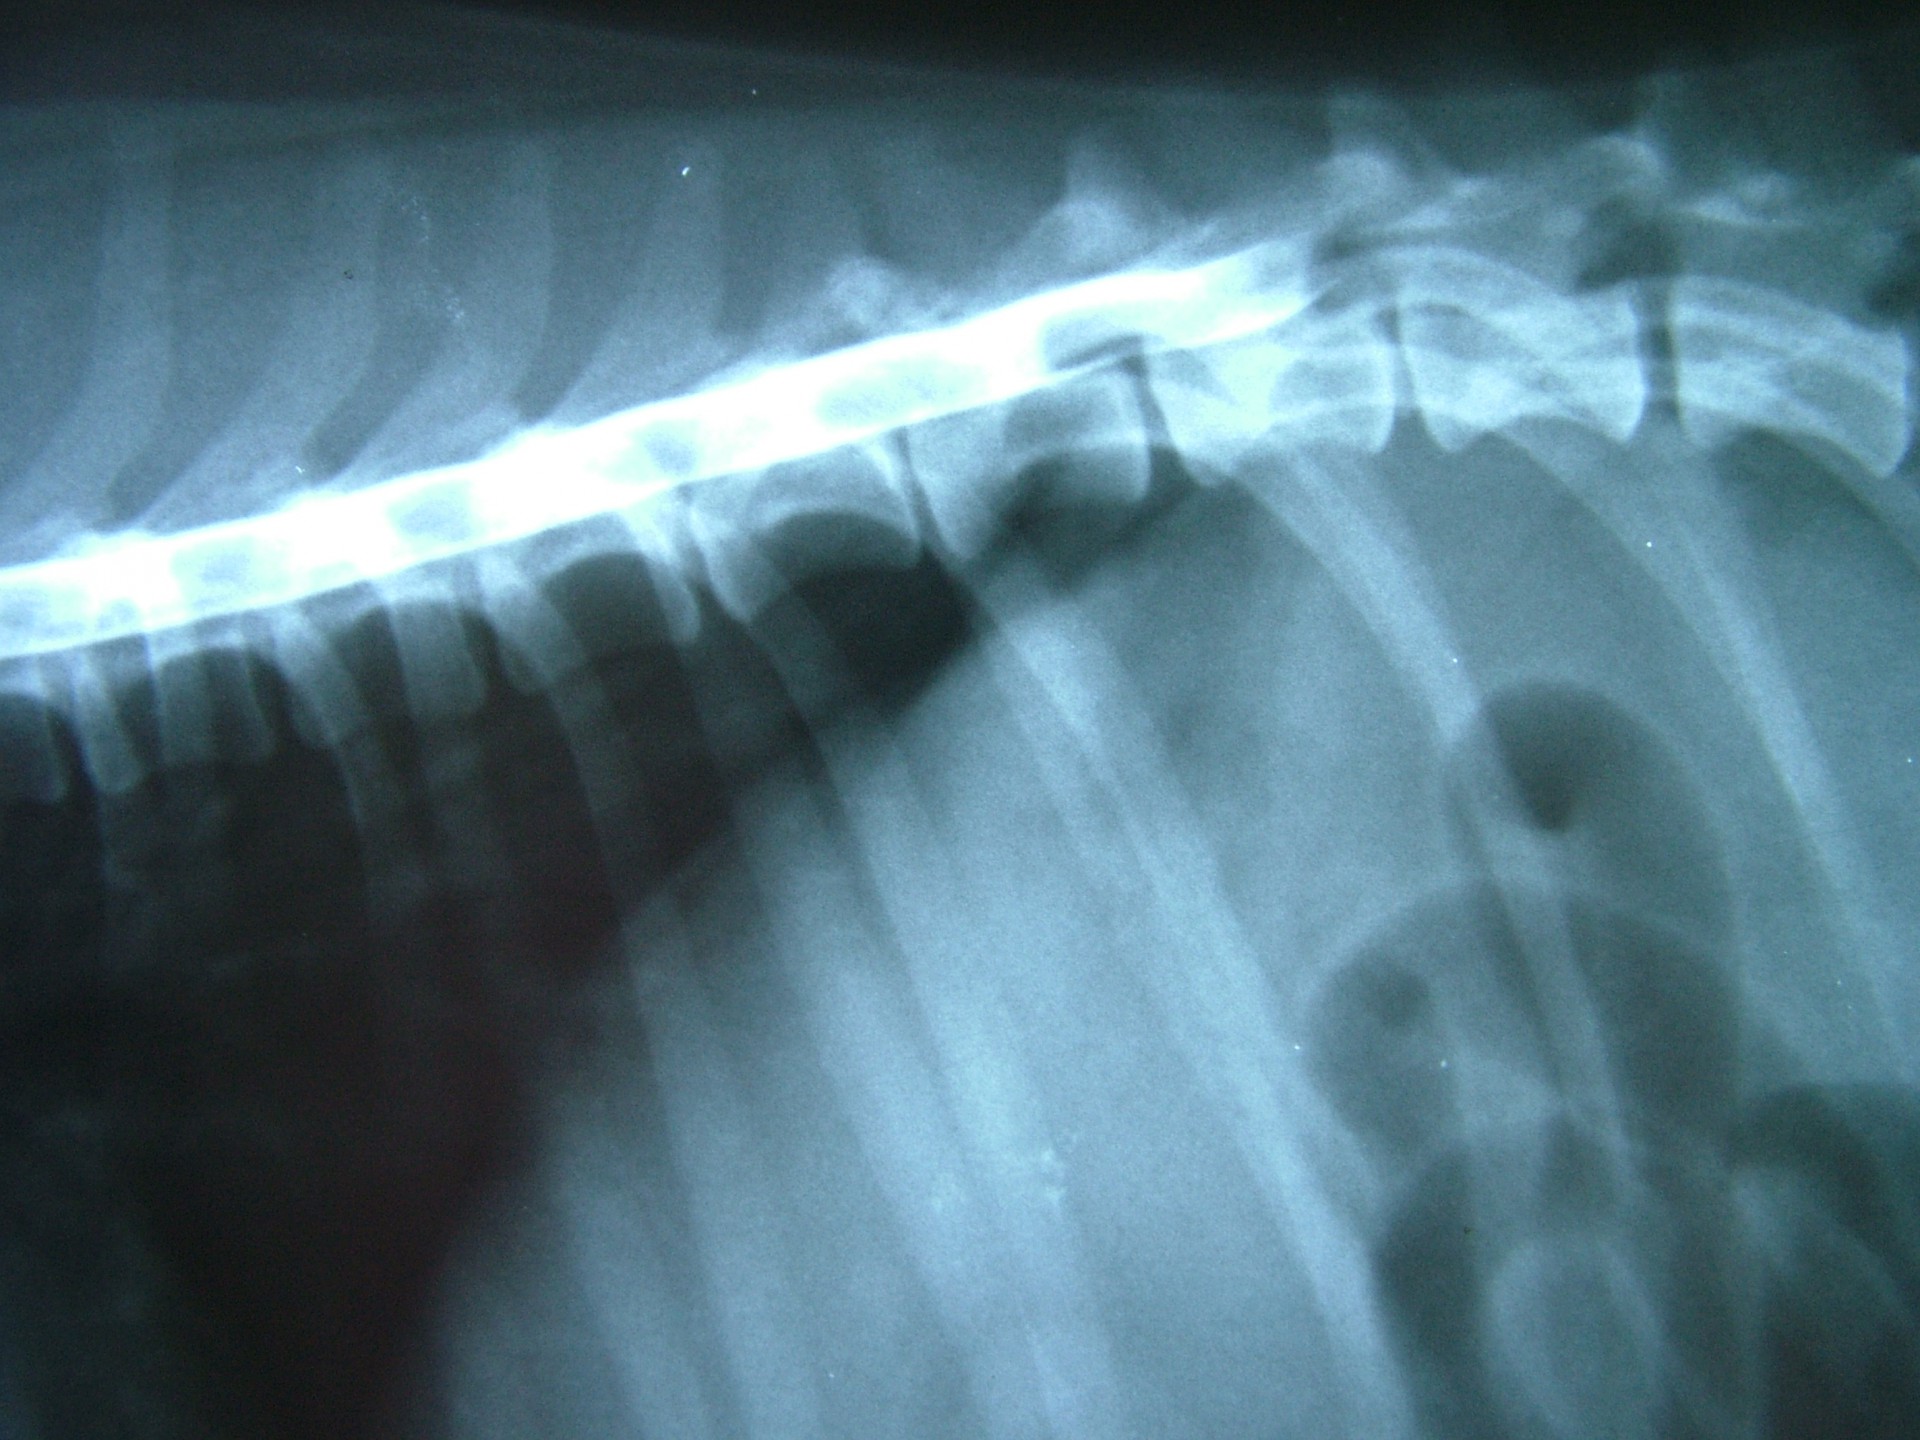

A myelographia során egy, a röntgen felvételen látható kontrasztanyagot juttatunk a gerinccsatornába, pontosan a gerincvelő és az azt körülvevő un.: kemény gerincburok (dura mater) közé. Ezt követően az állatot kb.: 45°-os szögben egy erre alkalmas asztalon lógatjuk, így a kontrasztanyag addig folyik a gerinccsatornában, amíg a gerincvelőt összenyomó porckoronghoz ér. Az így készített RTG felvételen az összenyomatást okozó előesett porckorong helye egyértelműen, az oldaldetermináció pedig általában meghatározható.A myelographia nagy előnye, hogy a betegvizsgálat helyén, azonnal elvégezhető, hátránya, hogy az altatásban történő vizsgálat invazív beavatkozás, mely után különféle szövődmények alakulhatnak ki.